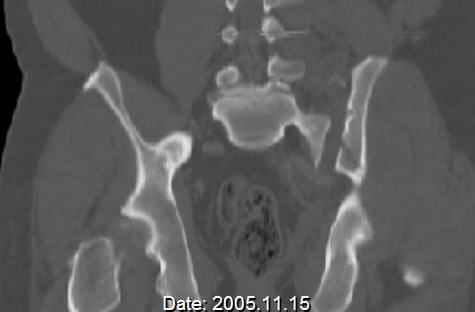

Hello gentlemen- Case is 52 YO male, fell out of treestand while deerhunting. He is 6 ft, approx. 260-275 lbs. Was hemodynamic unstable at local ER, sent to our Trauma center where circumferential pelvic binder placed and pt. stabilized with fluid, blood, and rewarming. Angiography not performed. An extraperitoneal bladder disruption was found, uro elected to treat non-operatively. Initial xray (not shown) demonstrated 5-7 cm wide at symphysis and SI joint. The first image attached is of CT once binder is in place. On post trauma day 5 the pt was taken to OR for ORIF of his iliac wing fracture and SI dislocation. The swelling/3rd spacing of fluid in the area of symphysis was profound, but quite acceptable posteriorly. Patient was prone for procedure, as I thought too difficult to fix the wing in lateral position. Of course the repair of wing was easy, but reduction of SI very demanding. The Floro images document the residual lack of reduction. That was the closest I could get it using 6mm joystick in wing, and clamp on sacrum and clamp through notch. The fixation was (initially) rigid. Anterior ex fix with supra-acetabular pins was placed due to condition of soft tissues, massive "beer-belly" overhanging the crest. Post trauma day ten patient's xray shows failure of posterior construct. Plan was to perform revision orif once soft tissues resolve considerably for full anrterior fixation and posterior fixation. However, while Im away for holiday (on Post trauma day 15), pt is developing septic clinical appearance, and trauma suspects pelvic abcess near symphysis and performs I and D - finds nothing but no primary closure performed. Posterior tissues/incision continue to look healthy. Now is post trauma day 17, pt is still tubed/on dopamine/and wbc still elevated, anterior incision still packed open. Clearly must get to bottom of possible sepsis, but then what? Thanks for you time - sorry for such lengthy clinical description. Thomas Schaller Kalamazoo, Michigan

Request for more images.. Axial and coronal recon (pt in binder.)